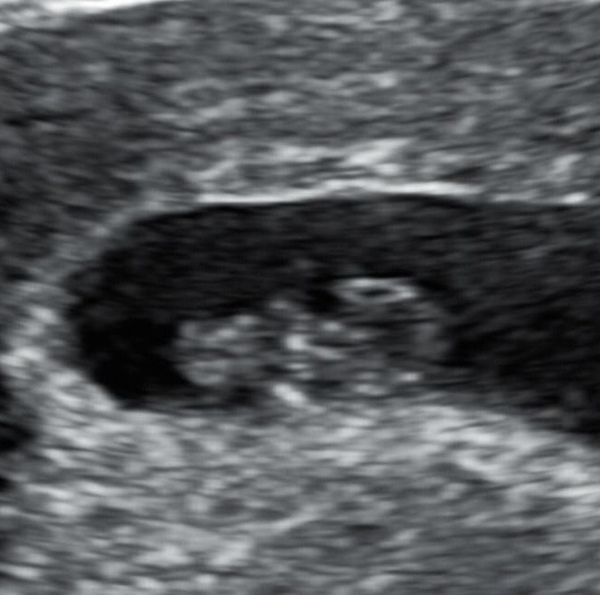

So, just in case anyone wants to see, had my 8 week 5 day scan today and it finally looks like a baby! Heartbeat still there, couldn't be happier!

Not sure why they've got the date of an old scan on there but it was this morning Smile